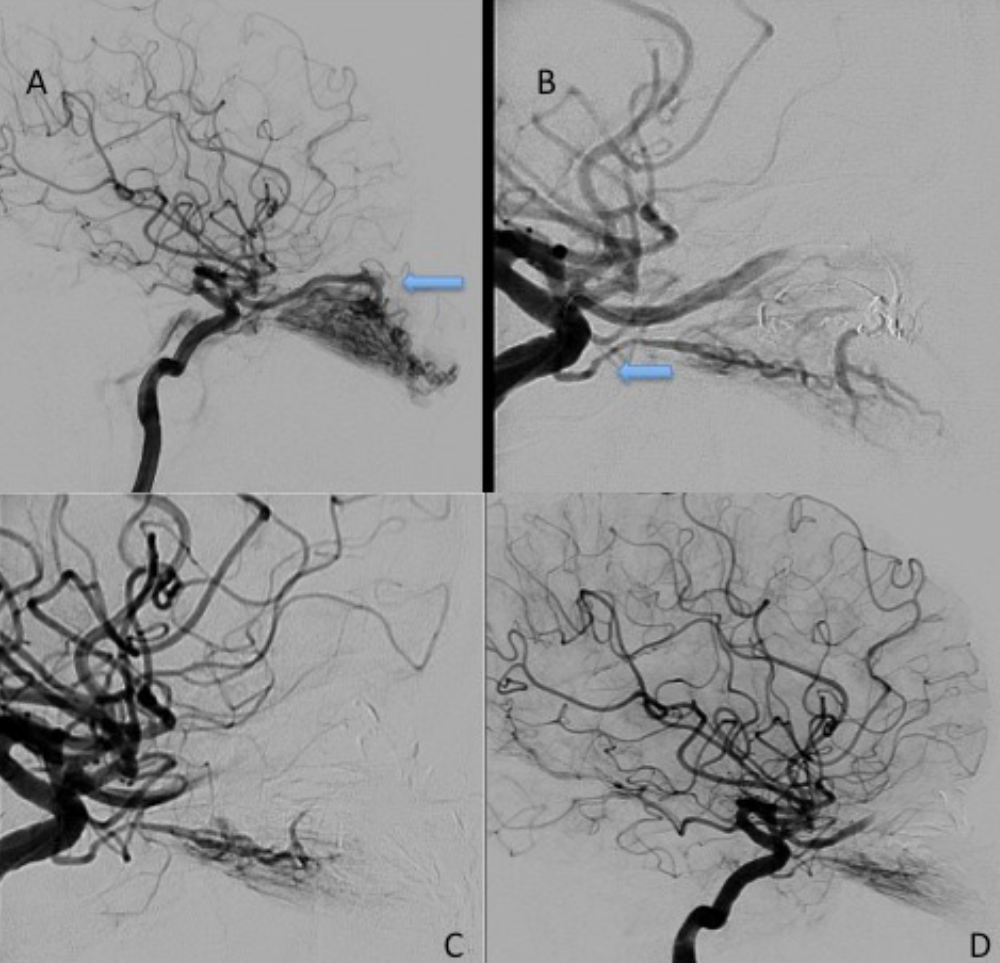

Figure 1. An example of PDOA. In the left globe, a hypervascular mass is observed and the mass is fed by (A) the left ophthalmic artery and (B) the left dorsal ophthalmic artery. (C) After embolization of OA, feeding from the dorsal ophthalmic artery is continued, and (D) retinal crescent staining is preserved